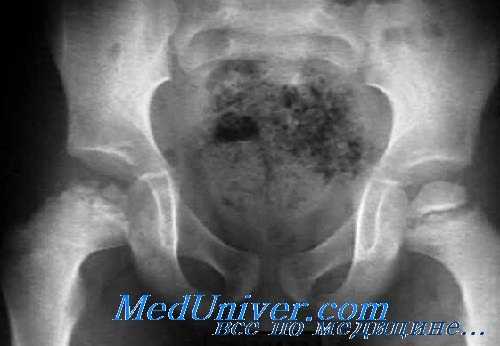

Рентгенография болезни Легга—Кальве—Пертеса

Ранним признаком болезни Легга—Кальве—Пертеса является расширение суставной щели и выбухание мягких тканей над капсулой с минимальным выпотом в суставе. Головка бедренной кости в вертлужной впадине может быть слегка сдвинута латерально. Через несколько недель головка бедра будет выглядеть более плотной, чем остальная кость, с последующей фрагментацией.

Появление фрагментации на спине — признак некроза; врастание новых сосудов стимулирует процесс реабсорбции. Это приводит к уменьшению плотности проксимального конца метафиза из-за усиленной васкуляризации и остеосклероза с расширением и укорочением шейки бедренной кости и увеличением плотности головки.

Стадия фрагментации занимает период от 1 года до 2 лет, вслед за которой наступает фаза регенерации, при которой в эпифизе формируется новая кость и окончательная форма головки варьируется в размере и очертаниях в зависимости от степени сплющивания, происшедшего ранее. В дальнейшем постепенно развиваются явления вторичного остеоартроза.